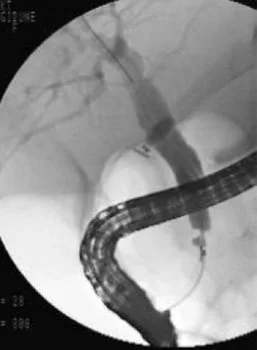

A

B

Figure 19. Jeune patiente ayant présenté un épisode de migration lithiasique, avec des calculs vésiculaires en échographie.Pendant la cholécystectomie, une cholangiographie peropératoire a montré une sténose cholédocienne. La bili-IRM (A) retrouve cette sténose, 15 mm en amont de la papille (flèche), avec dilatation de la VBP d’amont. On note par ailleurs un pancréas divisum, et la présence du drain biliaire en T laissé lors de la cholécystectomie. En IRM, aucune autre anomalie n’est notée en regard de la zone de sténose, y compris après injection de gadolinium. Ceci est confirmé par une échoendoscopie qui ne retrouve pas de syndrome de masse ni d’épaississement pathologique des parois biliaires. Une CPRE est réalisée dans le même temps (B) pour vérification cytologique par brossage et aspiration de bile, et mise en place d’une prothèse pour calibrage de la sténose. L’hypothèse retenue est celle d’une sténose bénigne, consécutive à une réaction inflammatoire sur lithiase enclavée puis secondairement évacuée